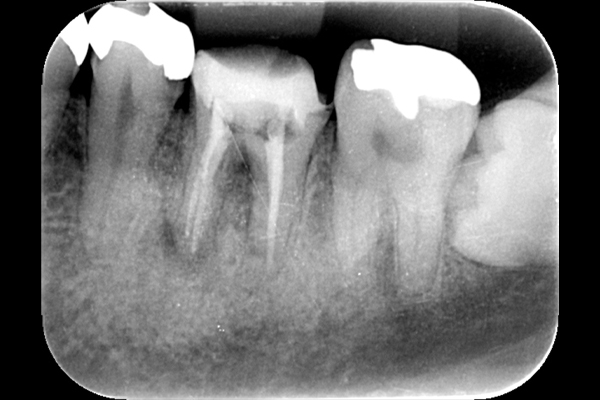

こちらは虫歯で神経を取らないといけなくなりましたが、何度治療しても痛みが消えないと言うことで当院にいらっしゃいました。度重なる治療で歯の神経のあった場所がかなりひろげられており、また根の先端も破壊されている状態でした。ですので、痛みが消えないのです。

肉眼では根の先端は見ることができませんがマイクロスコープでは見ることができます。根の先端をこれ以上破壊しないように清掃して歯の神経があった場所にお薬を詰めることができました。根の治療後、かぶせ物までして半年たっても痛みがありません。

レントゲンを見ていただいて、歯の先までしっかり白いお薬が入っているのがわかります。